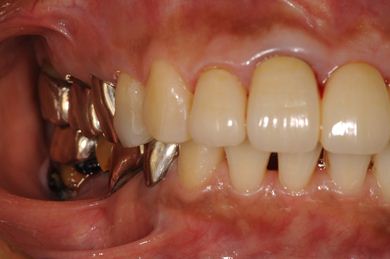

インプラントの症例写真 IMPLANT

インプラント治療+セラミック治療

| 治療内容 | インプラント2本、オールセラミック4本(ジルコニアフレーム、オールセラミック用の土台1本) | ||||||||||||||||||||||||||||||||

| 総治療費 | 1,299,000円 | ||||||||||||||||||||||||||||||||

| 治療期間 | 7ヶ月 |